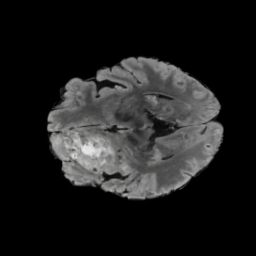

BRATS. The largest public dataset of brain tumours consisting of 5,880 MRI scans from 1,470 brain diffuse glioma patients, and corresponding annotations of tumours[4, 45, 5]. All scans were skull-stripped and resampled to 1 mm isotropic resolution. All images have a resolution of 240 240 155, and we use the flair T2 sequence. Tumours are annotated for 3 classes: Whole Tumour (WT), Tumour Core (TC), and Enhanced Tumour Core (ET).

Tumour Information Preservation. For the brain tumor segmentation, we use a Swin UNETR model[28, 70], trained with random rotation, and intensity as data augmentation. On the test set with human ground-truth annotations (), the brain volumes generated from single slice input preserve the volume of the different tumour components (paired t-test, for all 3 classes). In Figure 4, we highlight the tumor profiles of the generated MRIs compared to the ground truth tumour profile. The real MRI Dice score in the test set is 85.15 while the generated MRIs from a single slice have a dice score of 83.09. This shows how the generated MRIs indeed preserve the tumor information and can act as an affordable and informative pseudo-MRI, before conducting an actual costly MRI examination in hospitals. More detailed results are provided in supplementary material.